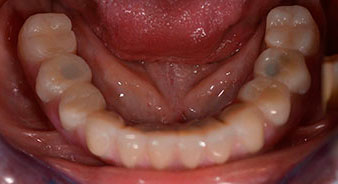

The 64-year-old patient presented with residual dentition of teeth 38, 33 and 43 and a clasp denture in the mandible (Fig. 1 and 2).

residual dentition

Fig. 1

Fig. 2